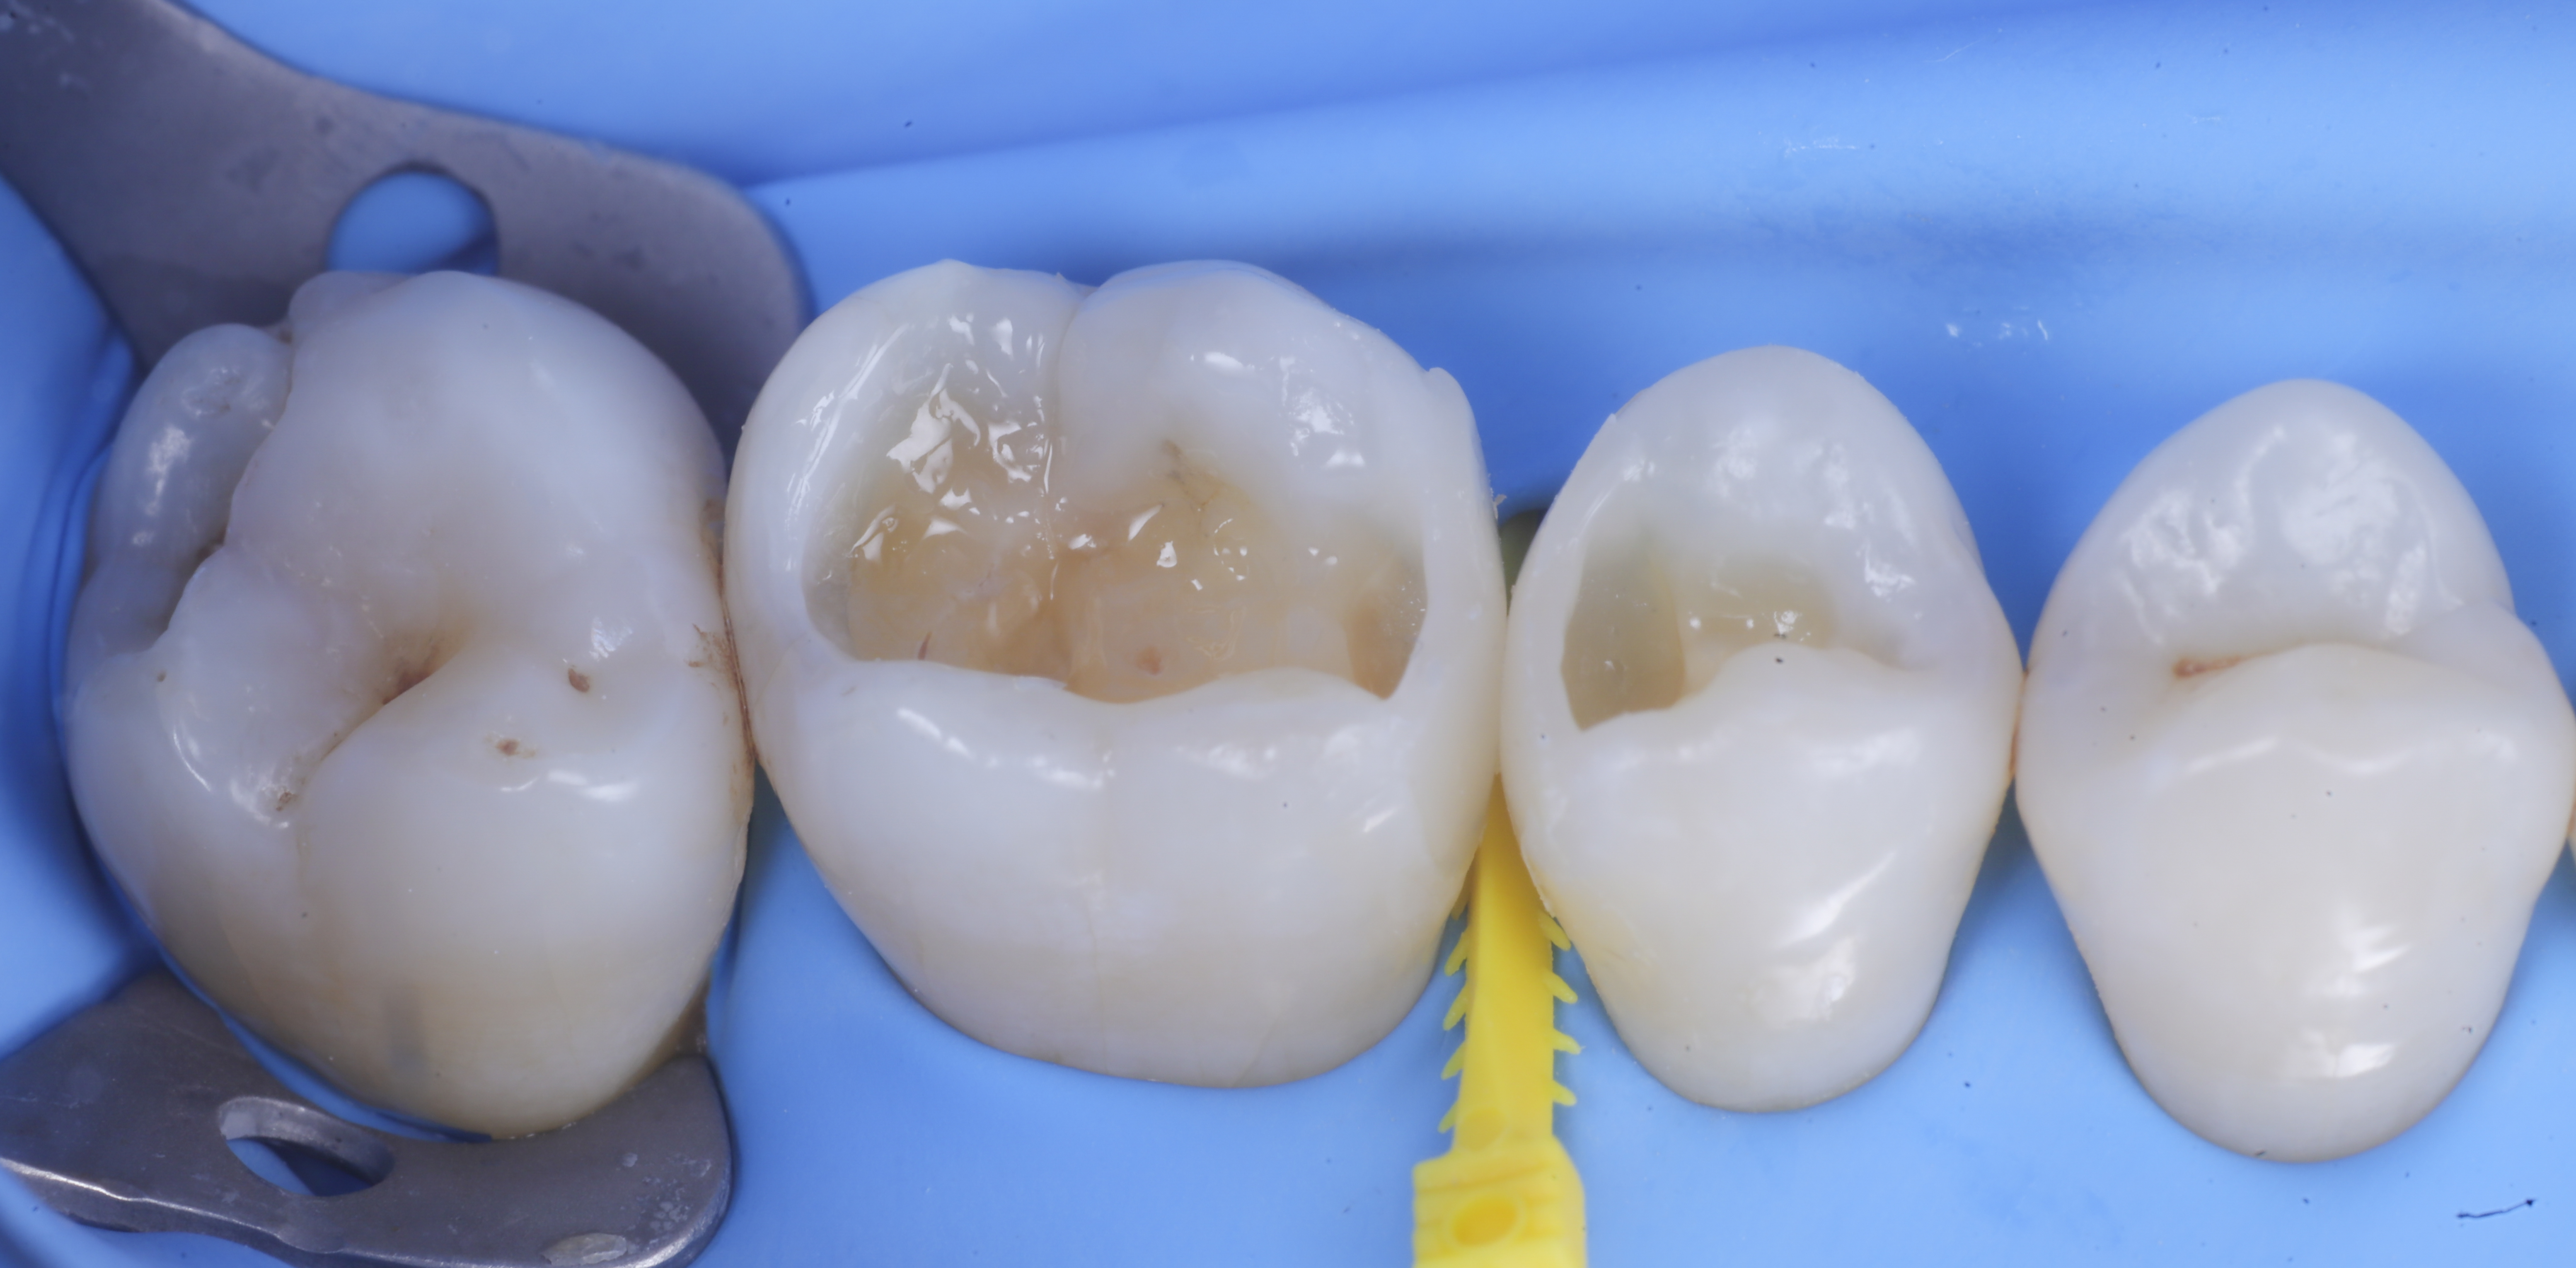

foto 8 Modellazione ed aspetto occlusale

foto 9 Modellazione ed aspetto vestibolare

foto 10 Modellazione ed aspetto palatino

Trasformate le cavita da II classi a I classi si procede con la classica modellazione cuspide per cuspide, sfruttando le caratteristiche meccaniche e anche estetiche dei materiali compositi bulk.